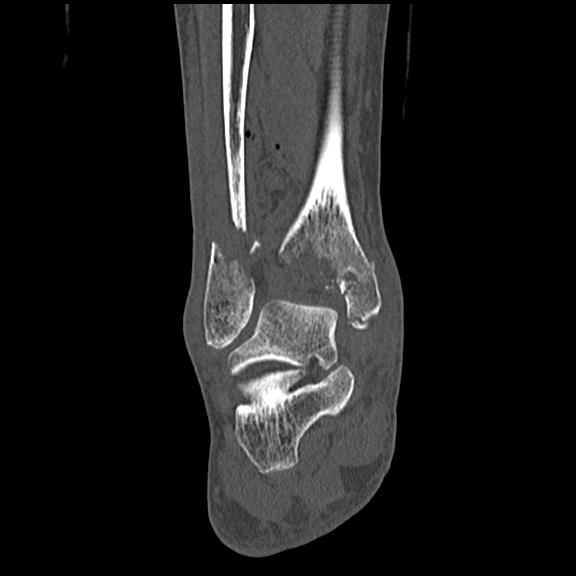

102755 1/4 2R 1/15 2R 右足関節 68歳女性 右三果脱臼骨折